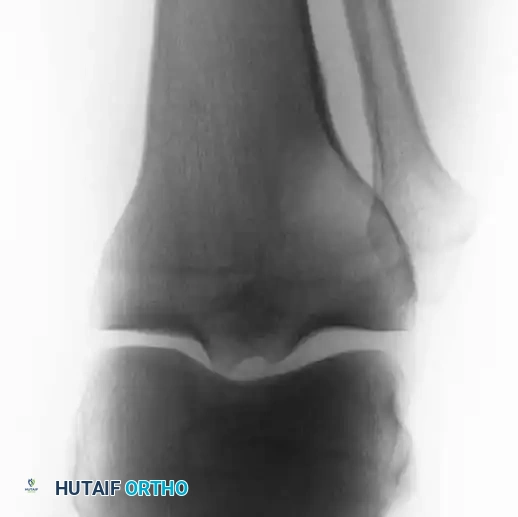

Postoperative radiographs demonstrating successful extended curettage, cementation, and screw augmentation of a distal tibial lesion.